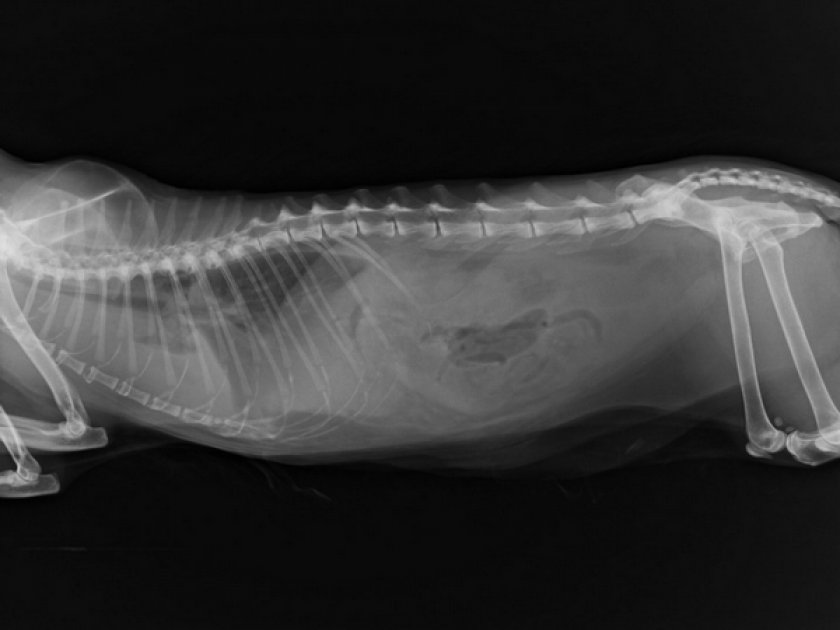

Рентген с контрастом — метод позволяет выявить аномалии в мочеполовой системе (опухоли, камни).

Рентген брюшной полости — метод выявления конкретно камней в мочевыводящей системе.

- рентген для выявления камней в мочевом пузыре или почках;